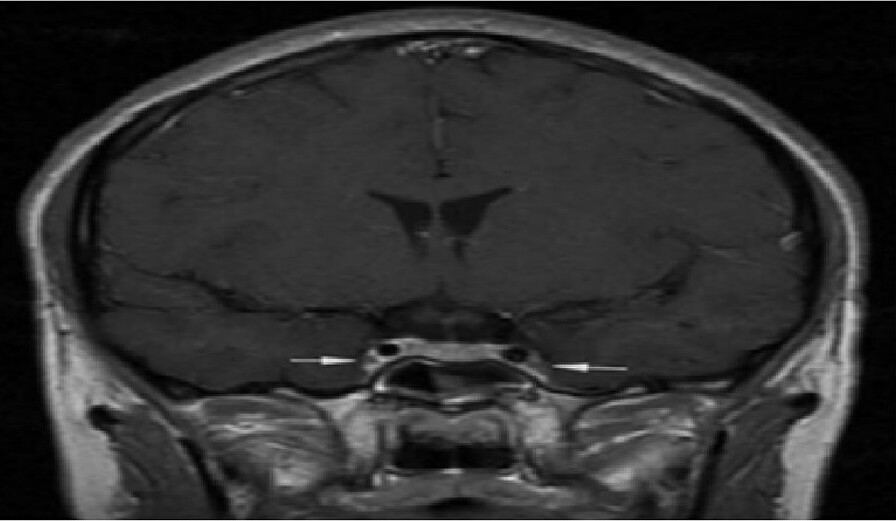

The arrows indicate inflammation and spasm of both internal carotid arteries. *Photo: Hospital provided*

Doctor Nguyen Huu Quan from the A9 Emergency Center stated that the patient's condition began with acute purulent sinusitis. The infection then spread, causing inflammation on half of his face, quickly leading to altered consciousness and seizures. Magnetic resonance imaging (MRI) of the brain revealed diffuse edema, a typical sign of cavernous sinus thrombosis—a rare infectious blood clot condition at the base of the skull.